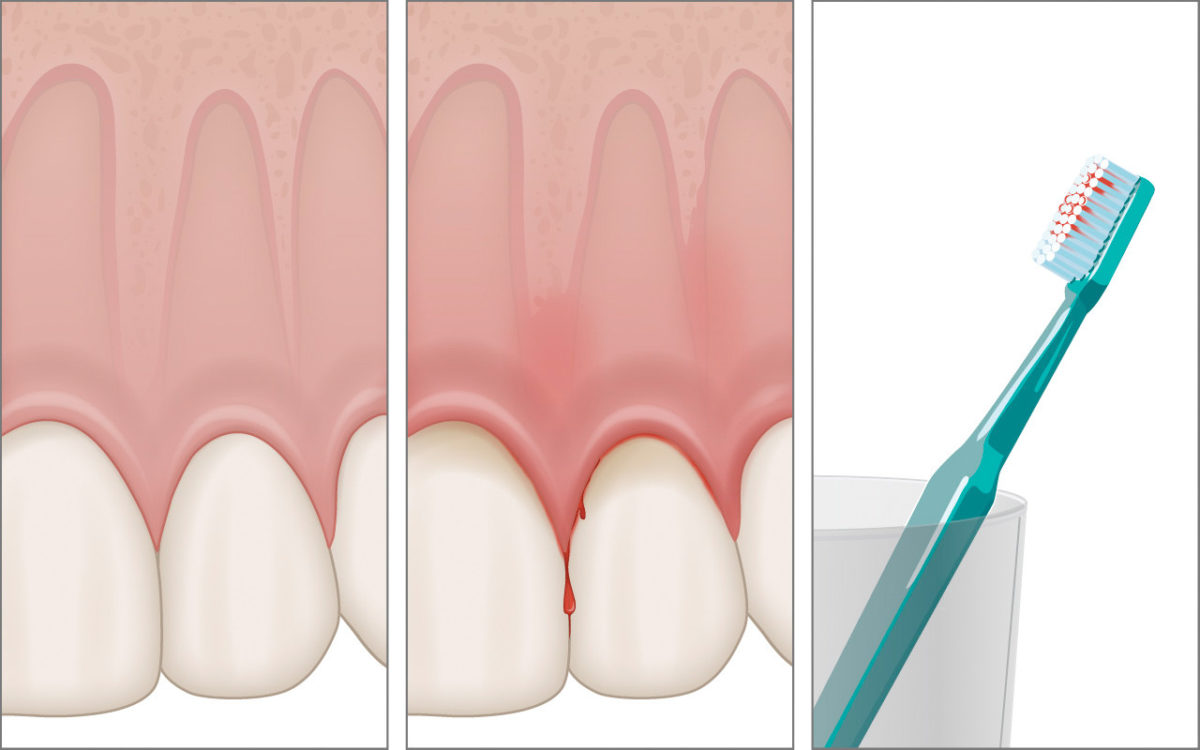

Erste Anzeichen einer Zahnfleischentzündung sind eine Rötung und leichte Schwellung des Zahnfleischrandes sowie ein mögliches Bluten beim Zähneputzen.

Mehr …Zahnfleischbluten

Erste Anzeichen einer Zahnfleischentzündung sind eine Rötung und leichte Schwellung des Zahnfleischrandes sowie ein mögliches Bluten beim Zähneputzen.

Werden die Zähne jedoch bei der häuslichen Mundhygiene wieder regemässig gereinigt, gehen bei einer zuvor vorhandenen Gingivitis diese Zeichen der Entzündung innerhalb von wenigen Tagen wieder zurück.

Sollte das Zahnfleischbluten trotz guter Mundhygiene weiterhin auftreten, sollte das Zahnfleisch zur weiteren Aufklärung in der Zahnarztpraxis untersucht werden.